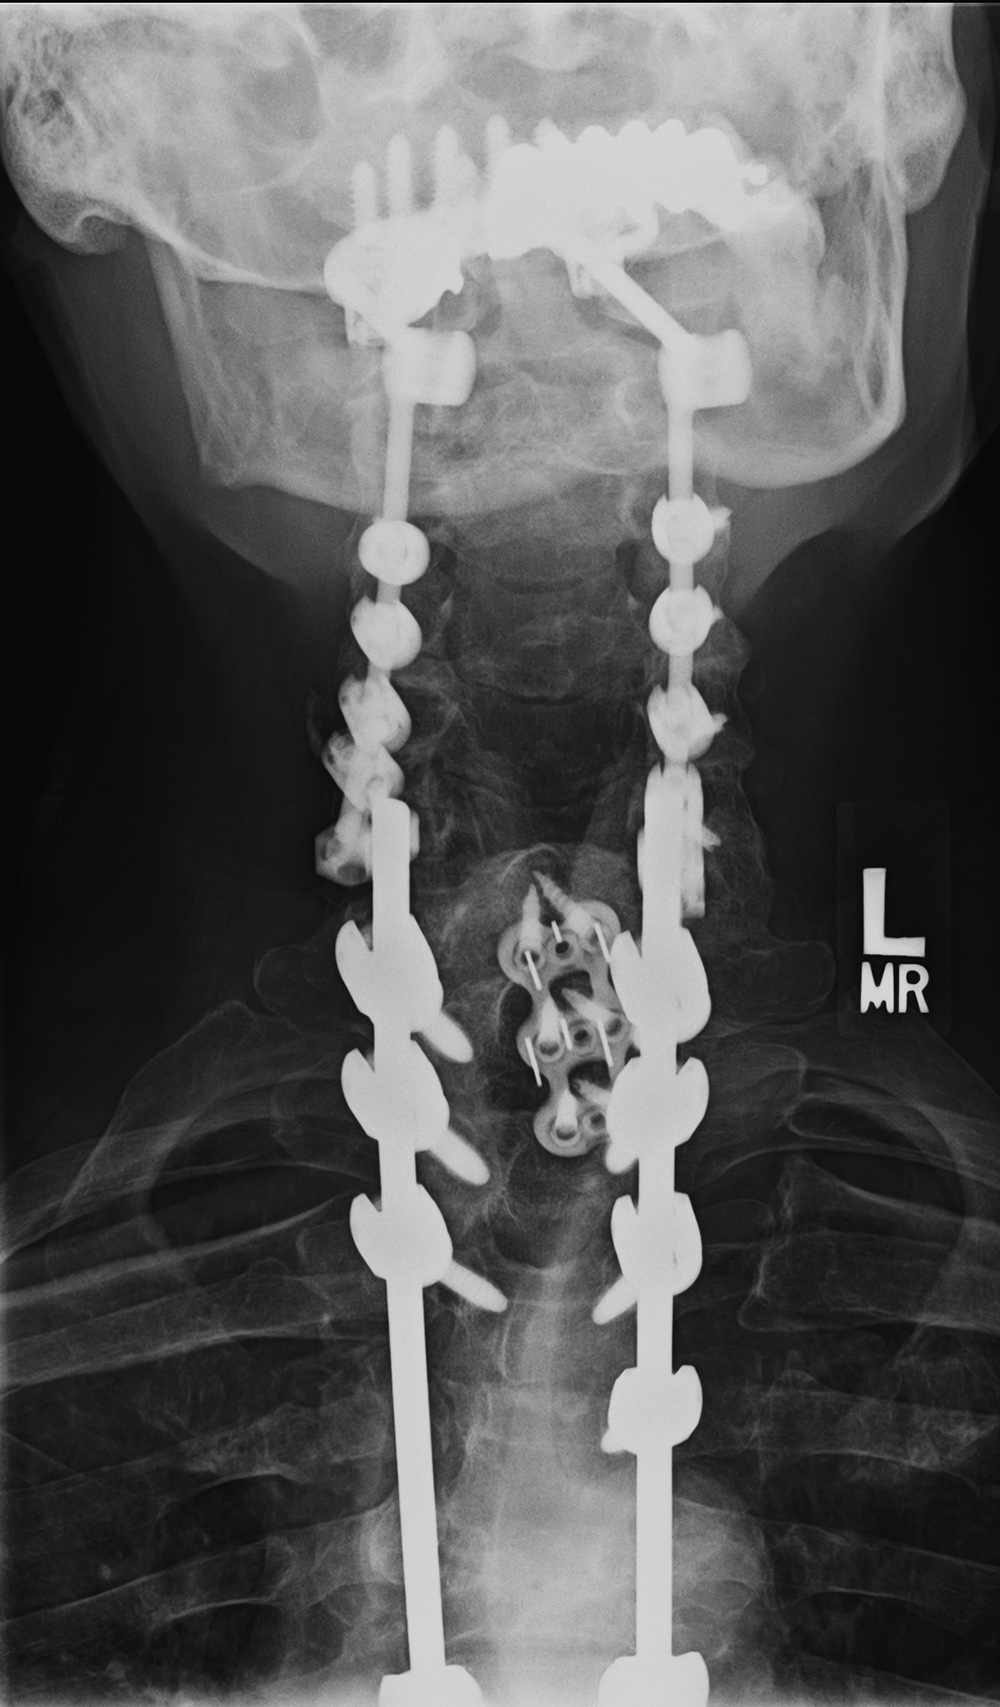

| Occiput-T8 posterior fusion with anterior cervical fusion from C6-T1. |

| 59 year-old man with occiput to T8 posterior fusion. There is anterior cervical fusion from C6-T1. PEEK disk cages are present at C6-7 and C7-T1. An old compression fracture is present at T5. In the cervical spine lateral mass screws are at C3-6 bilaterally. In the thoracic spine pedicle screws are at T1-3 and T6-8 on the right and at T1-4 and T6-8 on the left. Laminectomies have been performed from C3 to C6. |